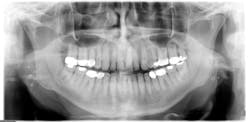

Radiographic assessment: Small, multiple, radiopaque, ill-defined, calcareous objects are seen on the radiograph (see Figure 1). The radiograph presented in this column was taken in 2015 of a 76-year-old male.

These opacities are not limited to the palatine tonsils but may also be seen in accessory lymphoid tissue. Sometimes what is referred to as "ghost images" appear on a pantomograph, making a pseudotonsillolith visible on the opposite side. This occurs because the object is located between the X-ray source and the center of rotation of the cassette. The patient may have oral calcifications bilaterally or unilaterally, so further evaluation is always needed.

Differential diagnosis: Diagnosis is made by radiographic assessment of the location exhibiting the oral calcifications. Calcifications may be found in other areas of the body such as within the molar-ramus region, including sialoliths, phleboliths, calcified lymph nodes, carotid artery arteriosclerosis, stylohyoid ligament ossification, and dystrophic calcification in acne scars (Bamgbose et al., 2014) Calcifications can also occur throughout the body - not just oral tissues.